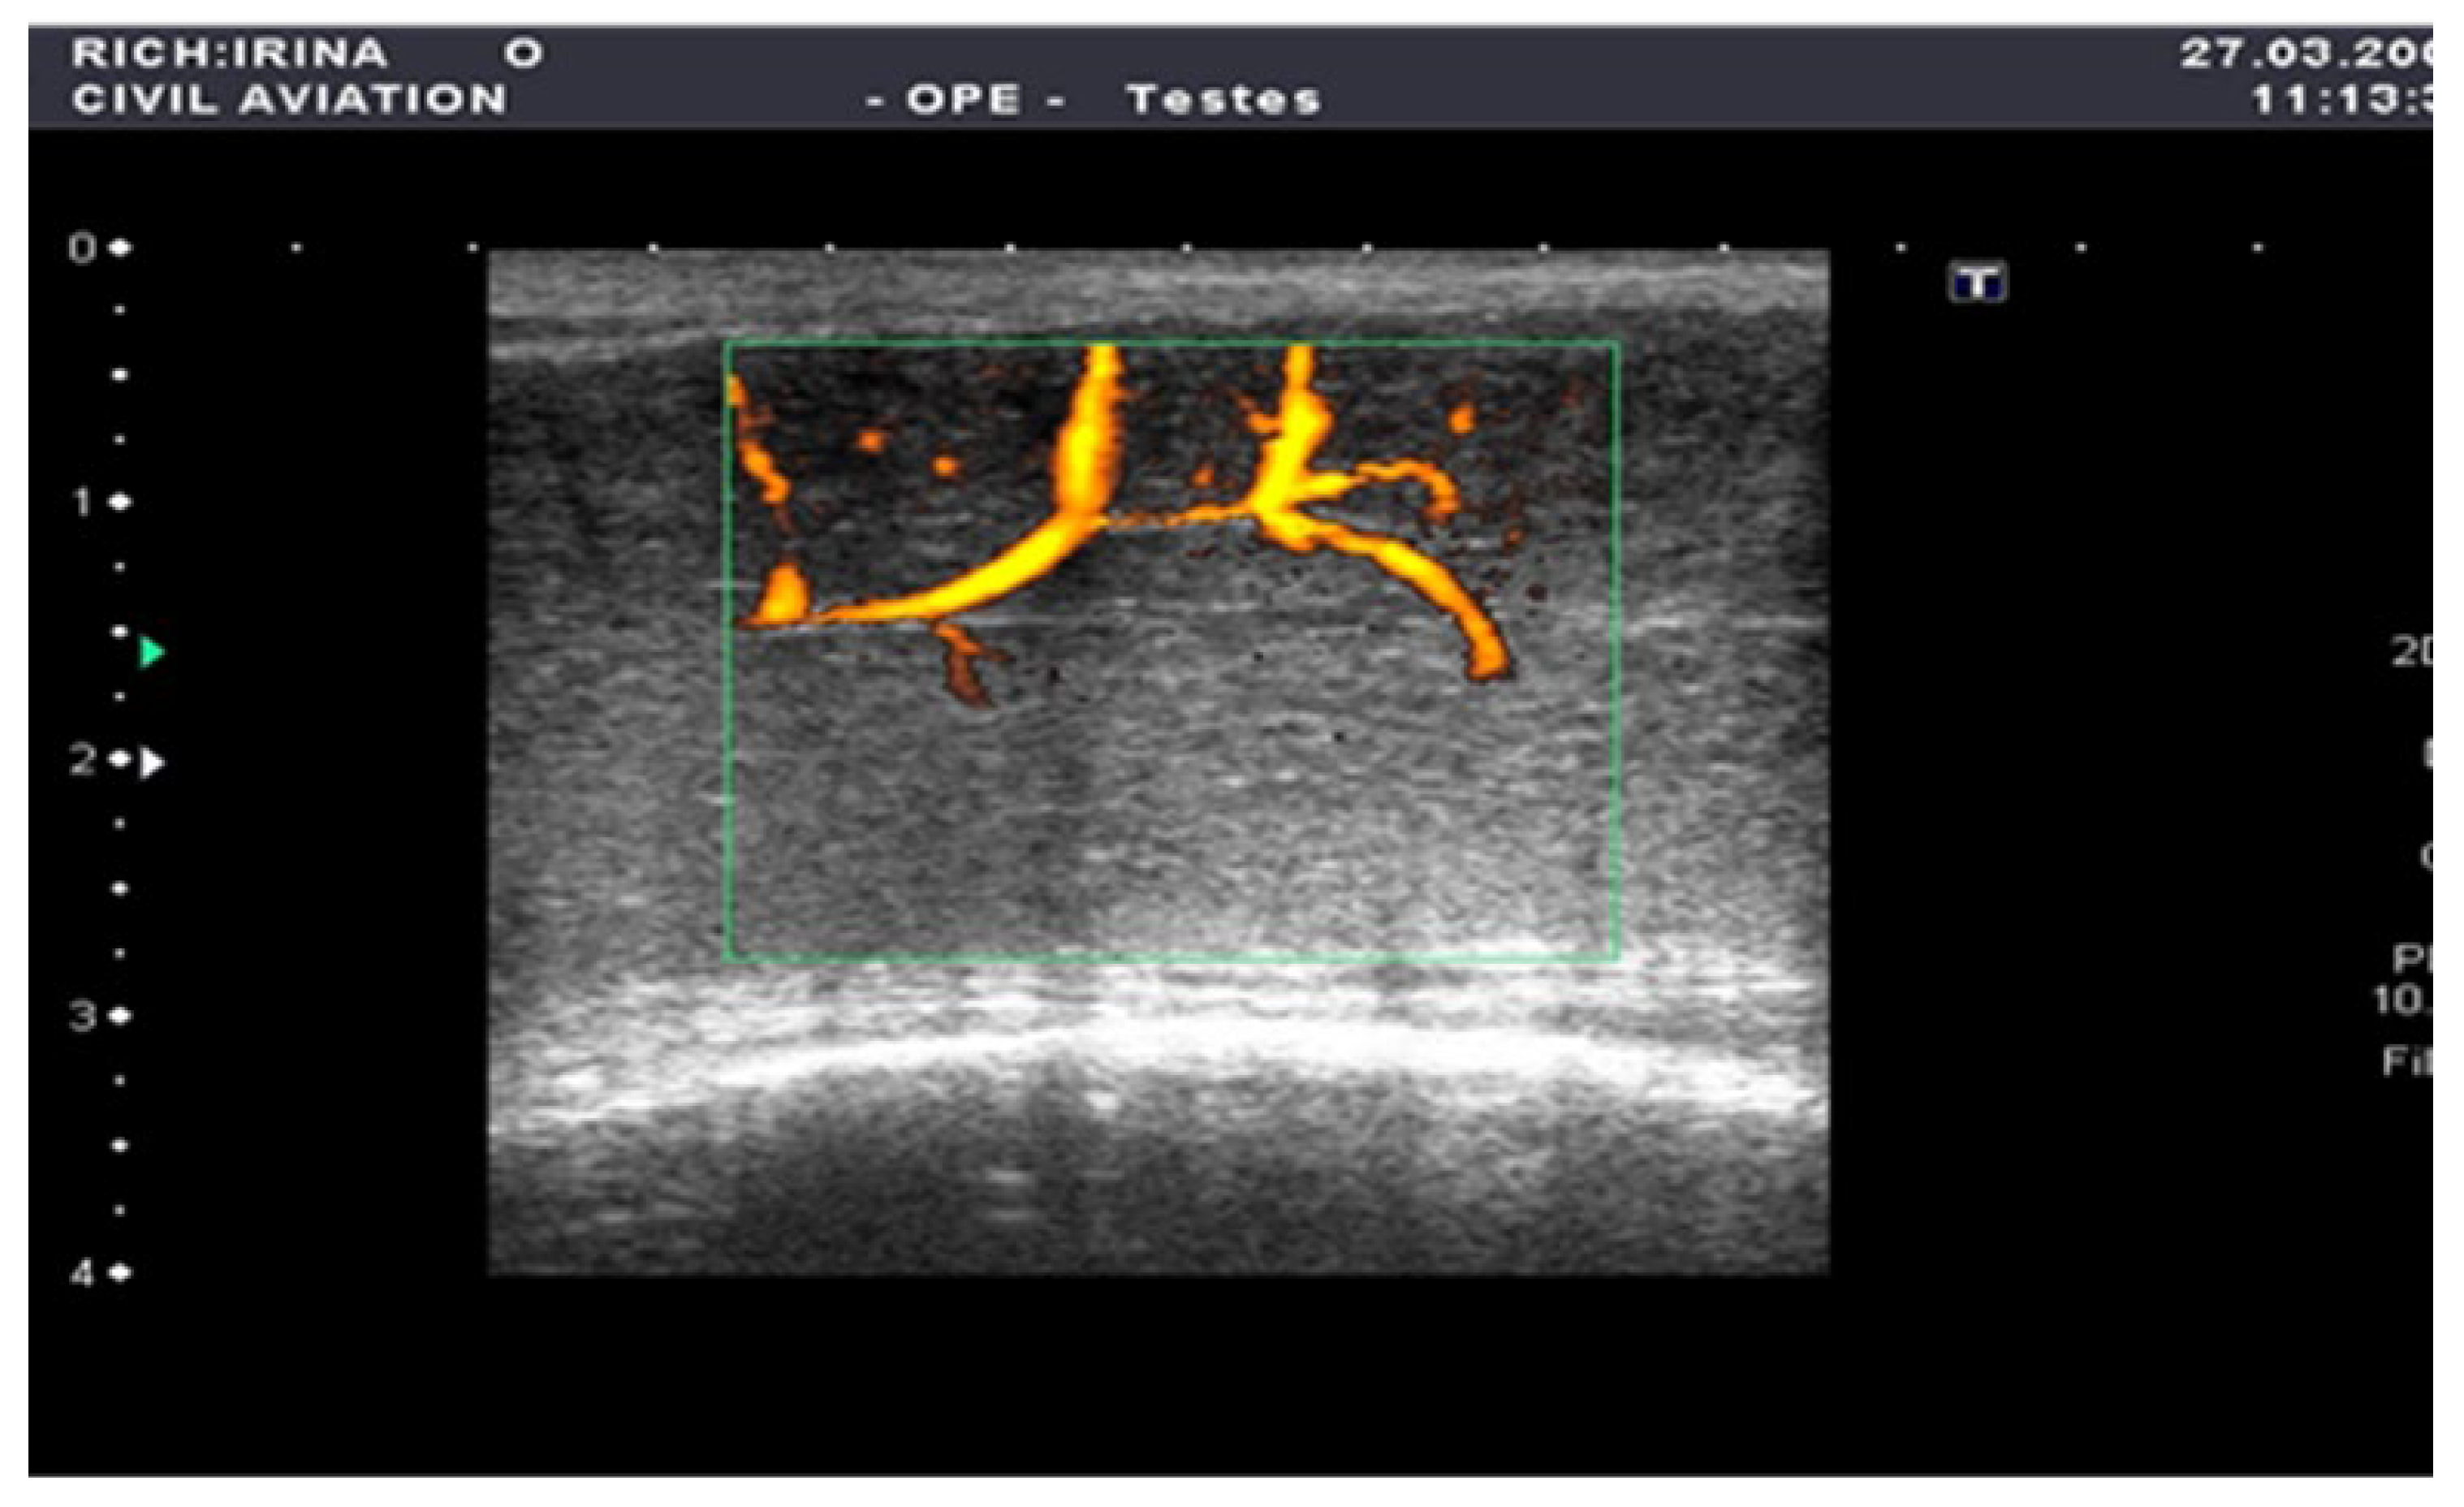

The penile CDUS revealed that 50 (56.8%) patients had ED signs, and 38 (43.2%) patients had no structural changes. Among these fifty males, 22 (25%) patients had penile arterial insufficiency (Figure 2), 17 (19.3%) patients had veno-occlusive ED (Figure 3), and 11 (12.5%) men had microcirculation disorder in the cavernous bodies of the penis (χ2 = 10.68, p = 0.002). Thus, the odds of detecting ED by using pharmacologically stimulated CDUS are 2.00 (OR = 4.47; 95% CI: 1.77 to 11.24).

Figure 2. Penile CDUS during pharmacologically induced erection. Signs of arterial insufficiency: visualization of arterial stenosis areas, with spiral arteries showing uneven and asymmetric contrast enhancement.